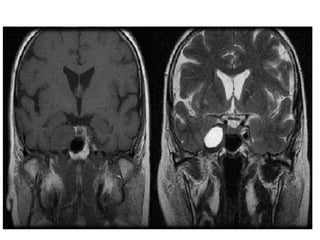

Pituitary adenoma Six to10% of pituitary adenomas invade the cavernous sinus,and represents its most frequent lesion. It is an intrasellar process with lateral extension to the cavernous sinus, in opposition to other diseases originating from the CS. These invasive pituitary adenomas are associated with more surgical mortality and morbidity. Macroadenomas (>1 cm) appear hypointense on T1- weighted image (WI) and hyperintense on T2-wi. They enhance after gadolinium administration, but less than normal pituitary tissue. Invasion of the cavernous sinus is secondary to the perforation of its medial wall, and is very likely if the lateral intercarotid line is crossed or if the encasement of the intracavernous ICA by the tumor is greater than or equal to 67%.

Invasion may bemore extended laterally after perforation of the lateral wall of the cavernous sinus. In general, they displace the ICA without narrowing.

• #27 Pituitary adenoma. Coronal T2-wi (a) and coronal enhanced T1-wi (b) showing an enhancing pituitary adenoma (arrows), appearing hyperintense on T2-wi and invading the left cavernous sinus with an encasement of the left internal carotid artery. Note the displacement of the arteries by the mass (stars) without stenosis.

• #28 Large enhancing pituitary mass extending to the right cavernous sinus and encasing the right ICA.